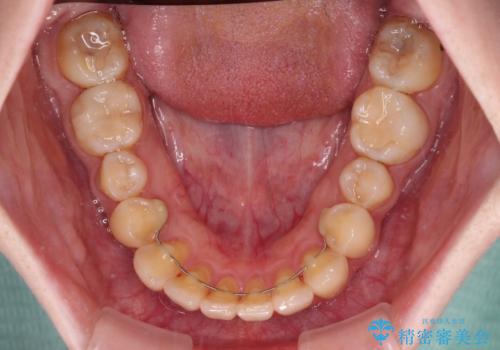

デコボコ歯列をきれいに インビザラインによる矯正治療

主に下顎歯列全体の後方移動とIPR(歯と歯の間を削る)によってデコボコが解消するように設計し、インビザラインにより治療を行うこととしました。

奥歯の知覚過敏が顕著となり、その影響で奥歯の咬み合わせ改善のための顎間ゴムの装着ができず、咬合を仕上げるまでに長い期間を要することとなりました。